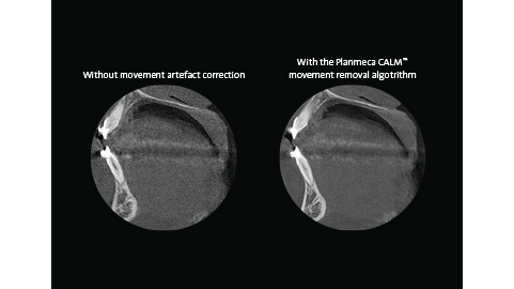

Patient movement is among the most significant challenges to CBCT image quality. When a patient moves during imaging, it produces artefacts that affect the quality of the image. The new Planmeca CALM imaging algorithm corrects these artefacts by compensating for patient movement. This leads to a sharper final image and helps prevent retakes.

Planmeca CALM is available for all Planmeca CBCT units. The algorithm works with all volume and voxel sizes and adds only under 30 seconds to the overall reconstruction time. The feature can be applied after the scan is complete, but also already before the exposure.